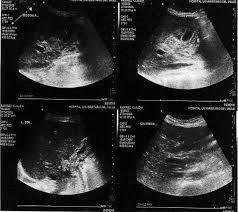

Ecografía abdominal: riñones de tamaño agrandado (14 cm) y eco estructura normal. No presenta ectasia pielocalicial. Hay esplenomegalia de 18 cm, con probables hemangiomas esplénicos y hepático